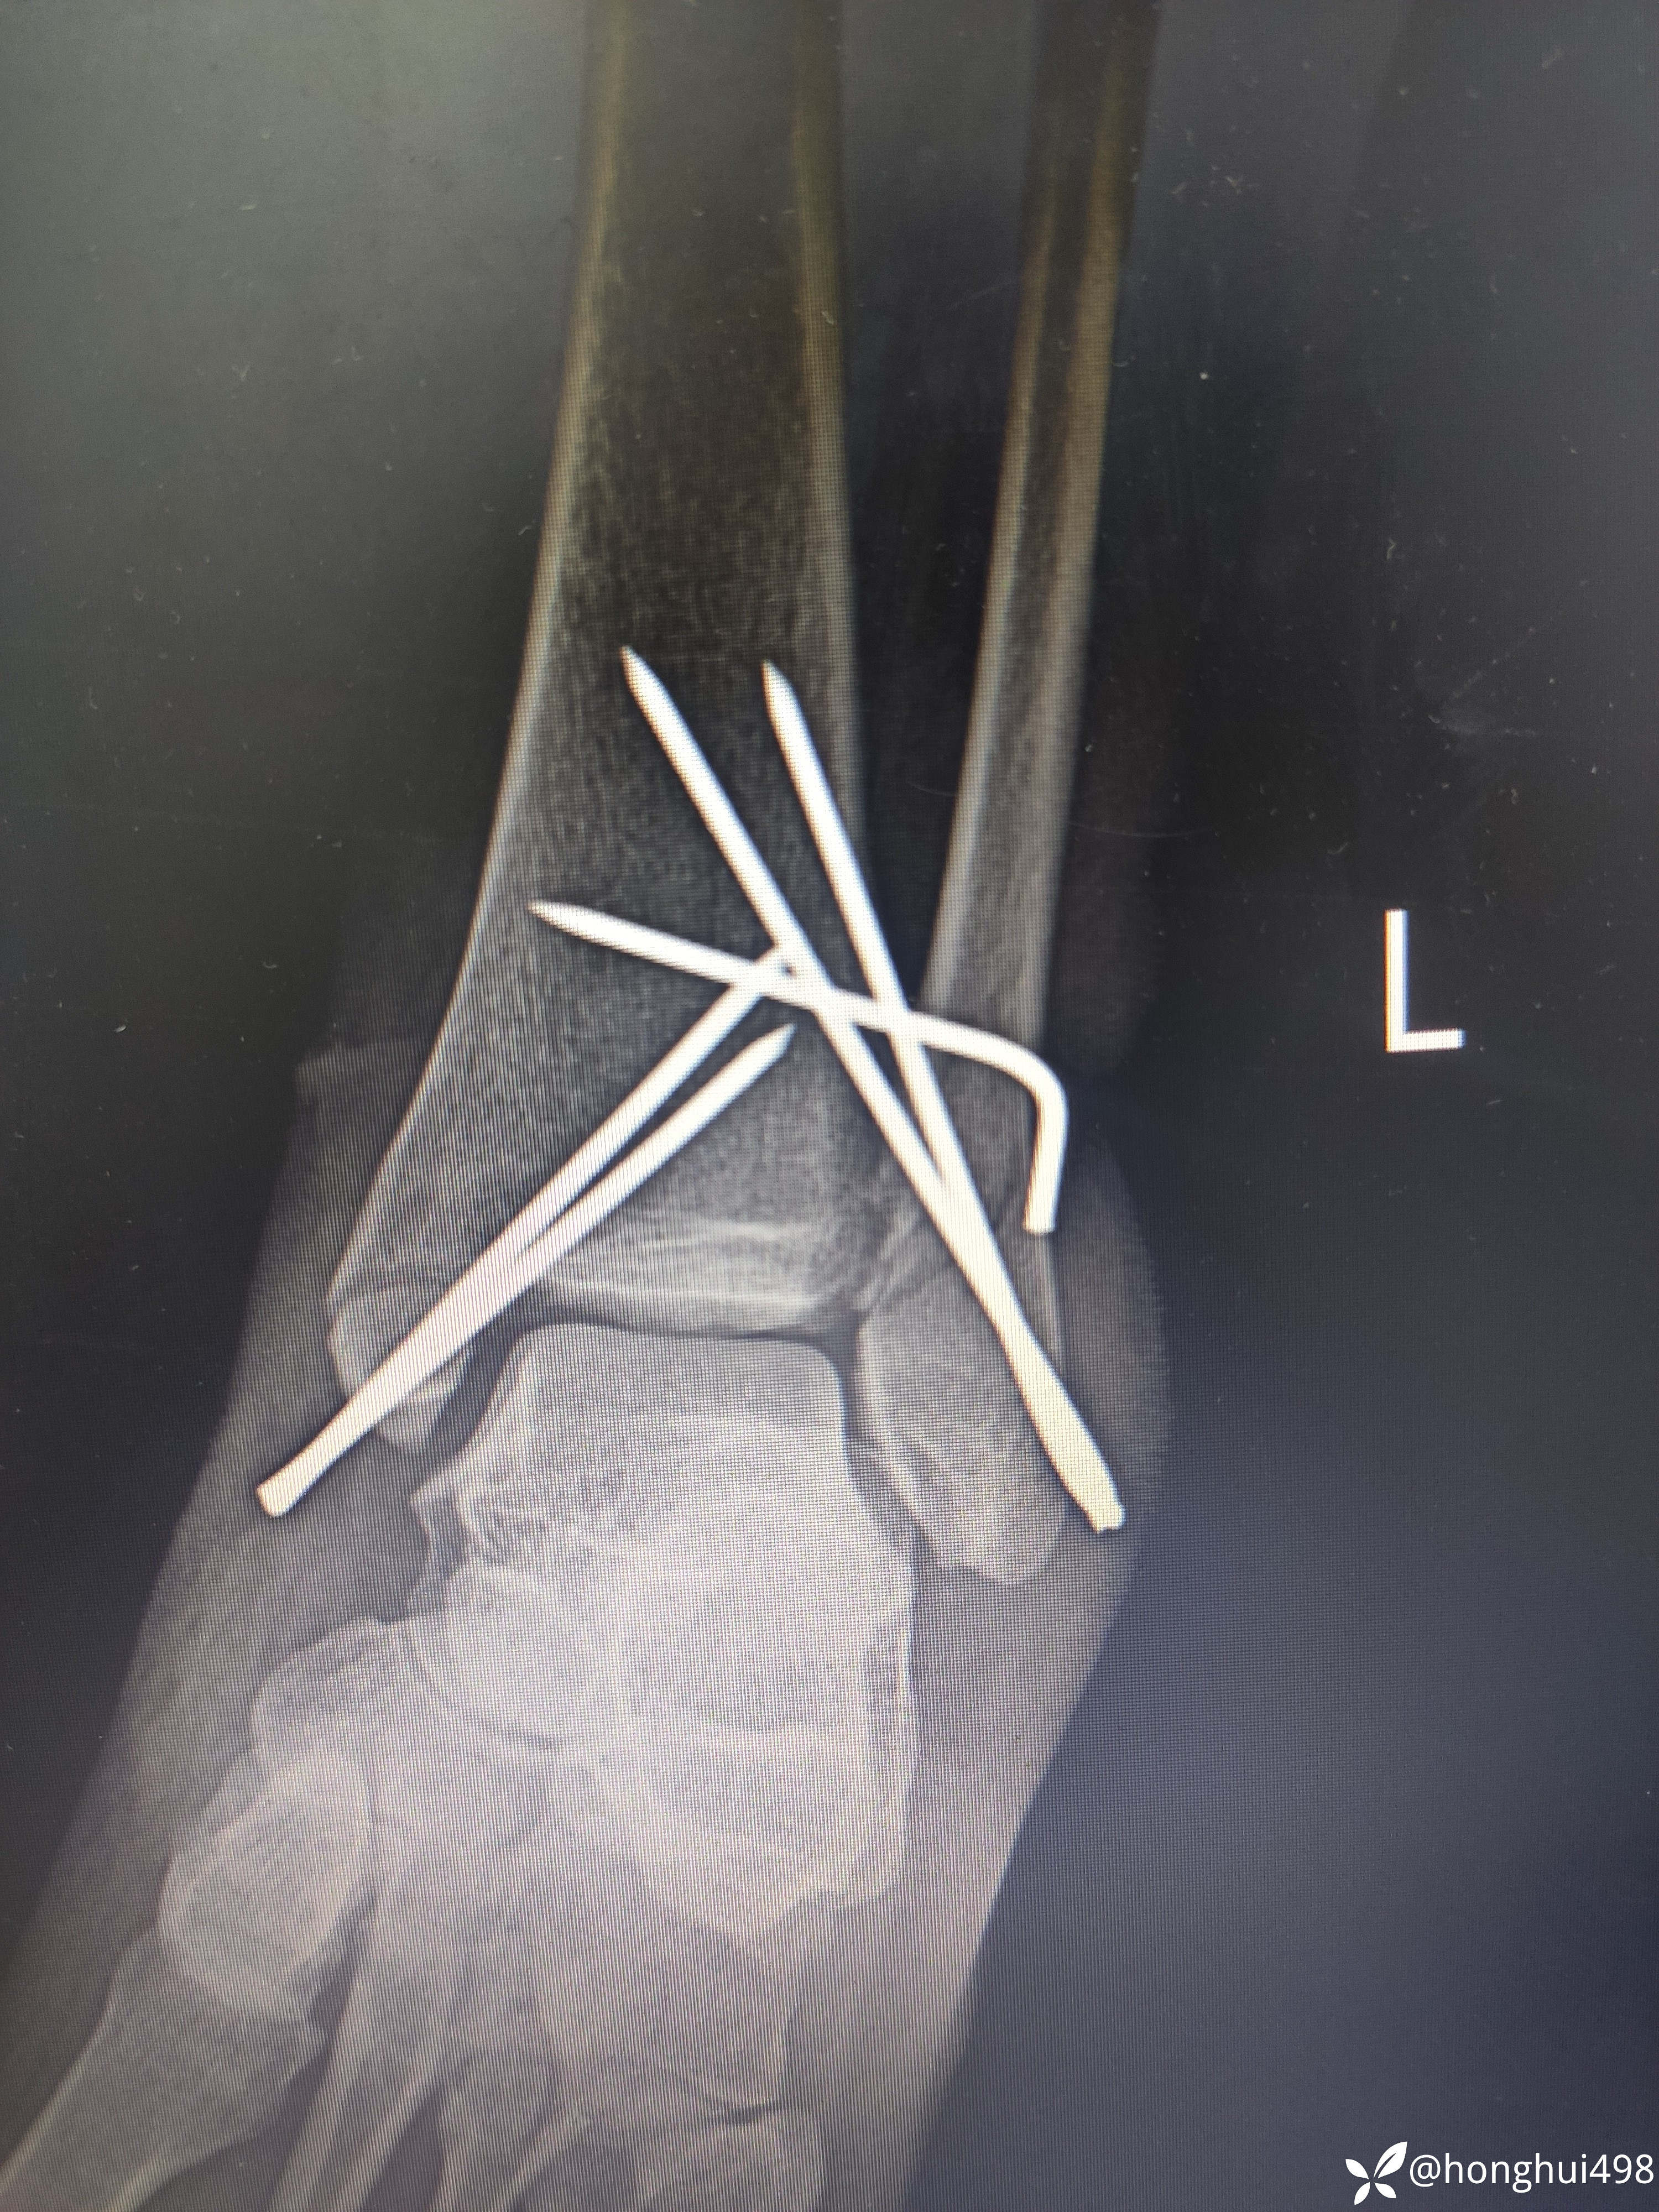

杨庆运骨伤科医生 达人已点赞女性53岁,因摔伤致左踝关节疼痛出血在当地私立医院手术治疗,据患者说内踝又挫裂伤口,诊断左踝关节骨折脱位开放性,予急诊手术克氏针内固定。术后第二天因子女都在城里上班为了方便照顾到我院要求住院治疗。

这看起来做的挺好,可是这下胫腓克氏针我该如何评价,该不该负重,等骨折愈合关节也僵硬了,如何规范治疗?